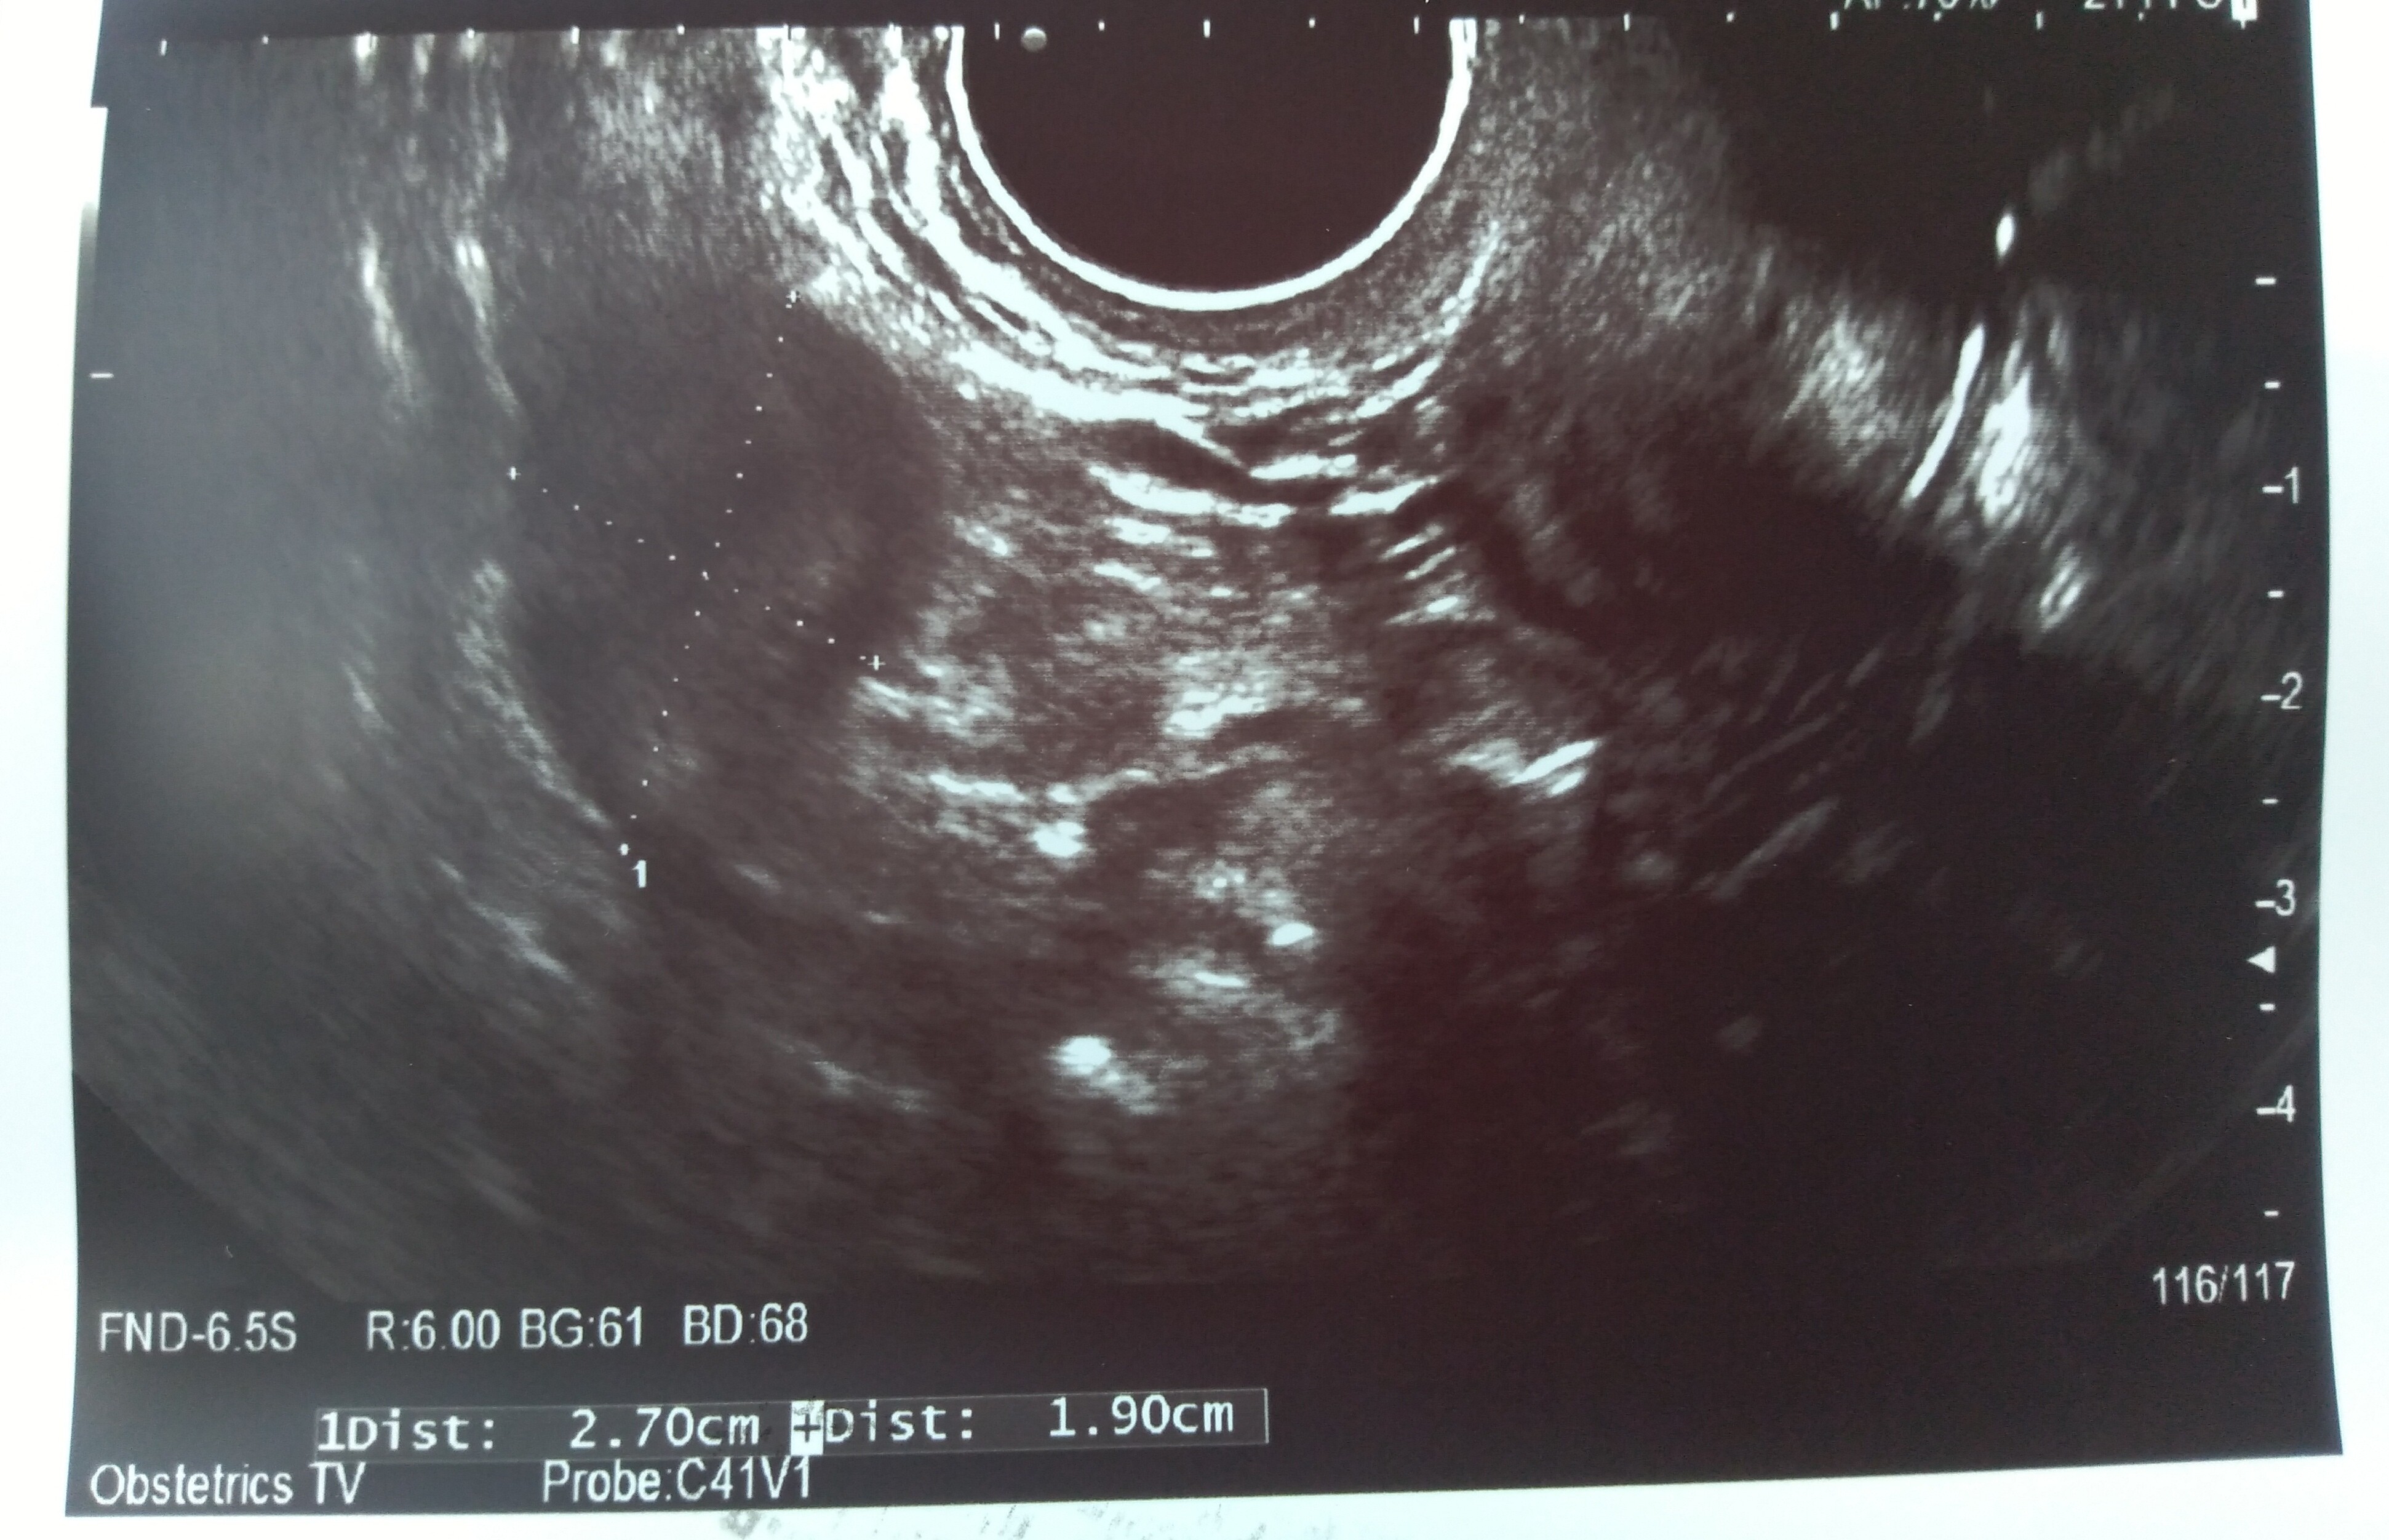

Hej dziewczyny, byłam na usg. Nie wiem co o tym myślećpowiedziała, że pęcherzyk ciążowy jest za mały na swój wiek. Ma 1,21 cm. Według aplikacji dziś 6+1

jest zarodek 2,9 mm. Serduszko bije 111/min. Nie puściła mi do słuchania tylko liczyła, widziałam jak faluje.

Jednak ciąża jakby jest młodsza o 2 tyg - usg pokazuje 4+2

Dodatkowo mam krwiaka większego dwa razy od pęcherzyka ciążowego - ma 8 na 5 i obok jakieś jeszcze mniejsze...

W razie krwawienia mam jechać na izbę przyjęć... Powiedziała, że ciąża wysokiego ryzyka, mam tylko leżeć. Karty ciąży nie założyła. Kontrola za 2 tyg. Dołożyła luteine i teraz mam 3 x1 duphaston, 2x1 luteina

Różowa strzałka wskazująca to krwiak. Te duże coś na 5 cm to nawet już nie wiem z tego wszystkiego co to było